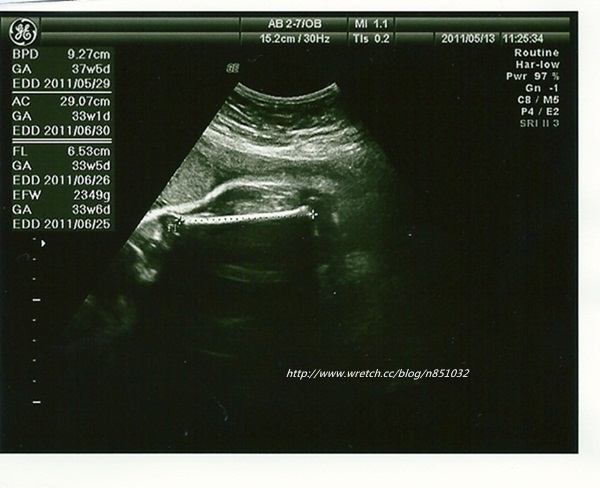

寶寶約40週的大小

二寶這次產檢比起上次增加了 639g

上次才在抱怨二寶的發展數值比同期的sophie小

沒想到這次就急起直追

胎位的部份還是不正

還有二寶的頭圍大了5周

有點誇張

醫生說腦部沒問題

就不用太在乎頭圍了